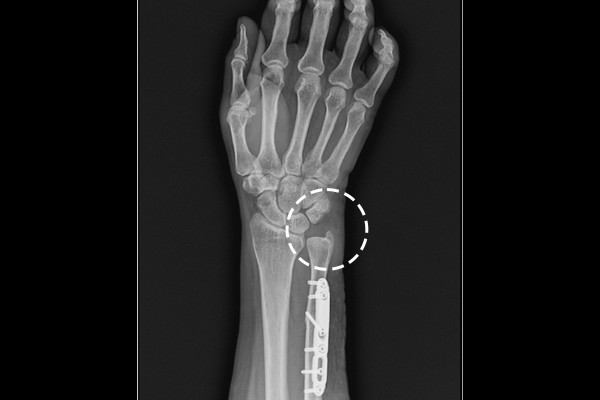

자세한 검사를 위해 영상의학검사중 X-ray검사를 진행하였고, X-ray 검사상 요골에 비해서

척골이 상당히 길었고, 동그랗게 있어야할 디스크 공간이 좁아져서 통증을 느끼는

우측 손목 척골 충돌증후군(Rt. wirst ulna impaction syndrome)으로 진단되었습니다.

수술을 하기로 결정하였고, 우측 손목 척골 단축 절골술 (Rt. wrist ulna shortening osteotomy)을

진행하였습니다. 척골 단축절골술은 길이가 길어 공간을 좁아지게하는 척골을 절골하여 높낮이를 맞춰주며

공간을 확보하는 수술입니다.